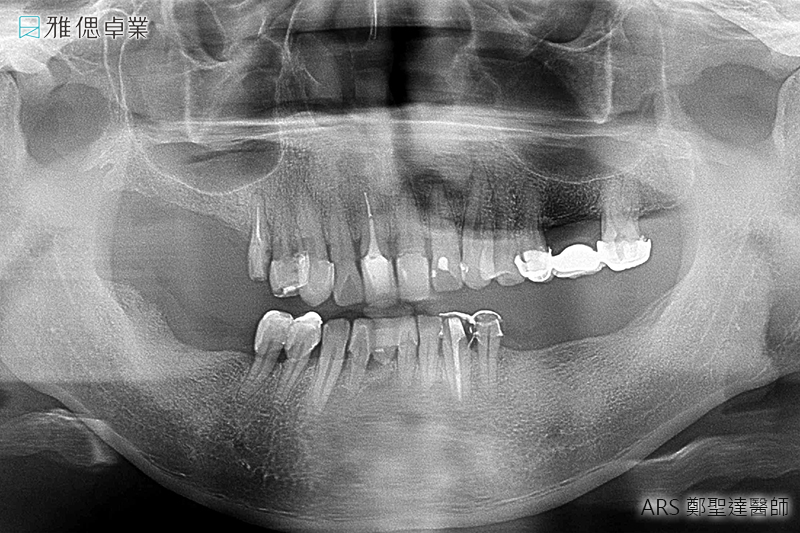

STEP1 諮詢、醫師診斷、收集相關資料與規劃療程

在醫師了解您的需求後,會拍攝斷層掃描、取得齒顎模型,製作數位手術導引板,擬定治療計畫,同時醫師會利用植牙模擬軟體,精準判斷植牙位置,提升植牙的成功率,讓植牙更精準、更安全。